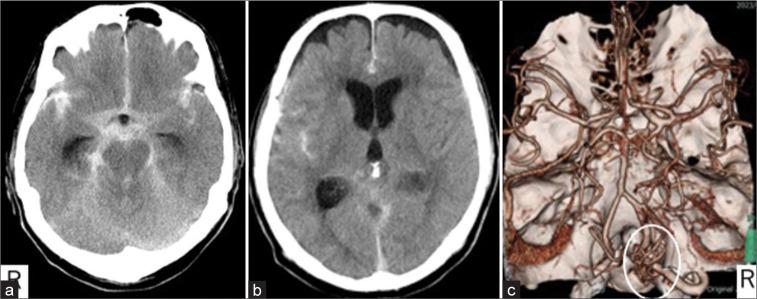

A 70-year-old man presented with a sudden onset of headache. He had Glasgow Coma Scale E4V5M6, world federation of neurosurgical societies (WFNS) Grade I. Fisher group 3 subarachnoid hemorrhage and hydrocephalus were found on head computed tomography. Cerebral angiography showed a spinal AVF at the C1 level of the cervical spine. Magnetic resonance image-enhanced motion sensitized driven equilibrium (MSDE-method showed an enhancing effect in part of the AVF draining vein, but the vascular architecture of this lesion was indeterminate. We performed continuous ventricular drainage for acute hydrocephalus and antihypertensive treatment. Cerebral angiography was performed 30days after the onset of the disease, and was revealed an aneurysmal structure in a portion of the AVF draining vein, which VW-MRI initially enhanced. On the 38 day after onset, he underwent direct surgery to occlude the AV fistula and dissect the aneurysmal structure. Histopathology showed that the aneurysmal structure was varices with lymphocytic infiltration, and hemosiderin deposition was observed near the varices.

一名70岁男性突发头痛。他的格拉斯哥昏迷量表评分为E4V5M6,世界神经外科联合会(WFNS)分级为I级。头部计算机断层扫描发现Fisher 3级蛛网膜下腔出血和脑积水。脑血管造影显示颈椎C1水平有一个脊髓AVF。磁共振成像增强运动敏感驱动平衡(MSDE)方法显示部分AVF引流静脉有强化效应,但该病变的血管结构不明确。我们对急性脑积水进行了持续脑室引流和降压治疗。发病30天后进行了脑血管造影,发现AVF引流静脉的一部分有动脉瘤样结构,VW-MRI最初显示该结构有强化。发病38天后,他接受了直接手术,以闭塞AV瘘并切除动脉瘤样结构。组织病理学显示动脉瘤样结构为伴有淋巴细胞浸润的静脉曲张,在静脉曲张附近观察到含铁血黄素沉积。